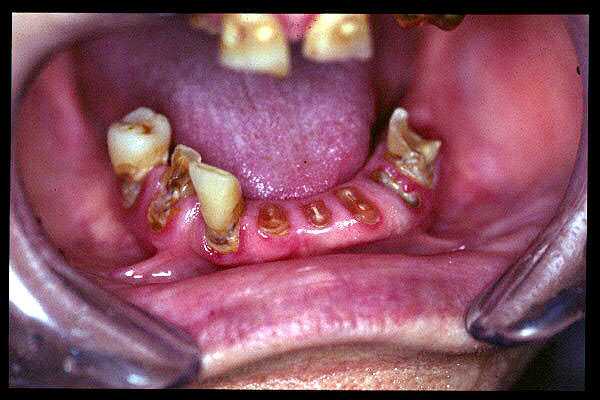

CM Edentulismo parcial, restos radiculares y caries